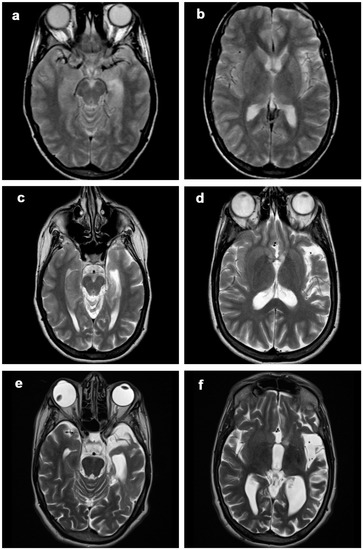

3.1. Atrophic Changes

3.2. Changes in Signal Intensity